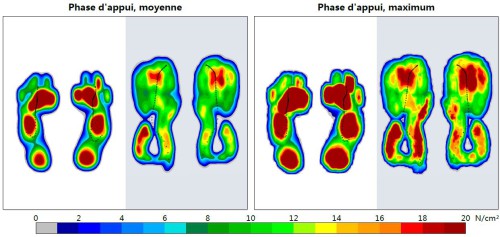

Ce qui saut aux yeux, ce sont deux choses : pieds nus l’appui du pied est très bien distribué entre l’avant, le milieu et l’arrière du pied. Ensuite, les orteils … ne jouent aucun rôle dans les différentes phases d’attaque. Les trois premiers métatarses engrangent presque toute la charge à l’avant du pied. Le talon est sollicité, mais pas plus que les autres parties du pied.

En chaussure amortie le patron est similaire avec toutefois un certain des-équilibre entre les deux pieds -à gauche je talonne, à droit, peu, mais je semble compenser à l’avant du pied. En tout cas, la présence d’une grosse semelle semble modifier l’endroit où le pied contacte le sol. J’ai surtout remarqué le poids des chaussures – c’était la première fois depuis 5 ans que j’en avais des comme ça aux pieds ! Je pense que ma foulée était moins rasante, et que je dépensais plus d’énergie à accélérer et les freiner, à vitesse égale. Très fatiguant.

Voici comment mes pieds attaque le sol. On mesure ici la pression (Newtons/centimètre carré) à 14 km/h à travers le pied. Je trouve (c’est quantitatif, hein ;-)) que l’impact se dispatche remarquablement bien entre les deux niveaux d’interférence entre le pied et le sol. Je pose clairement le talon, mais le plus gros de l’impact est sur le devant du pied. Bien ça.